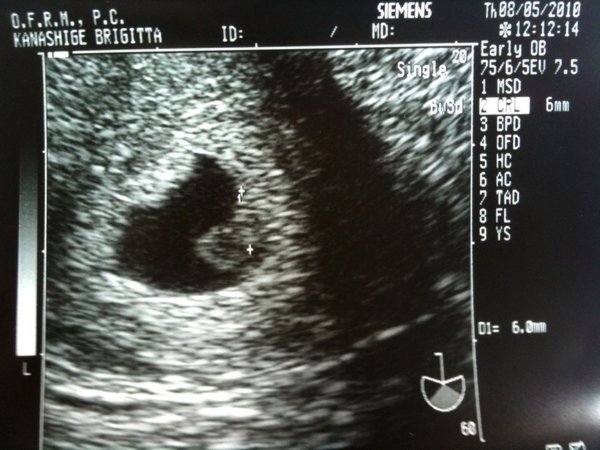

2.baba mar elejetol fogva mondtak ugye,hogy nem marad meg....de most voltam a specko uhun es csak petezsak van mar csak az is akkora mint baba A szal abbol mar nem lesz semmi

2baba volt egy van most a masik megallt a novesben es attol volt a verzesem is mert azzal elveteltem

6het